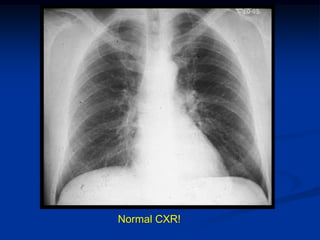

Normal CXR!